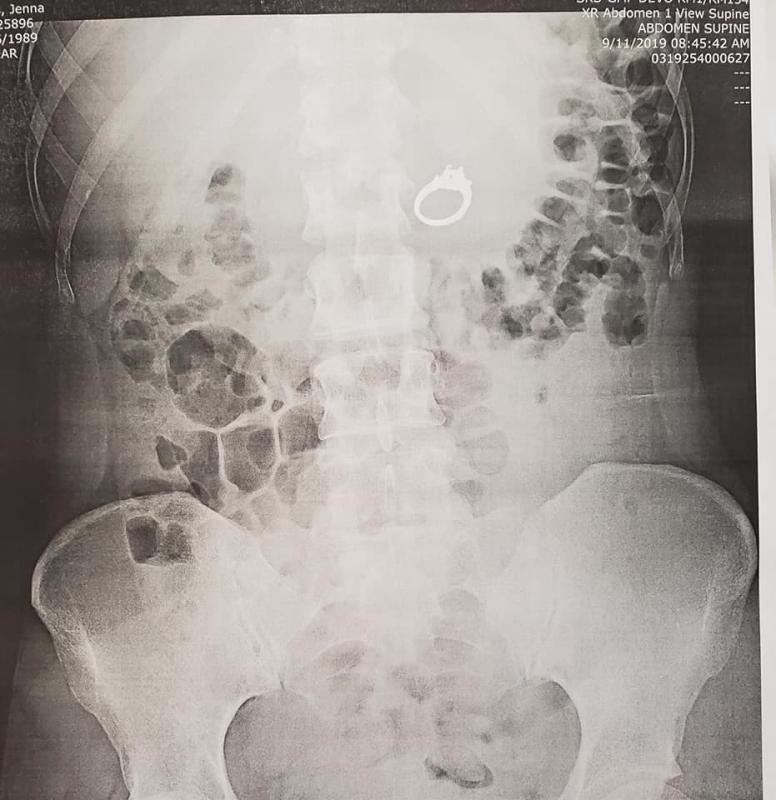

Al no encontrar el anillo, Howell y ella se dirigieron a urgencias donde pese a las risas contaron a los médicos lo sucedido. Tras las radiografías, le confirmaron que la sortija se encontraba en su estómago.

''Todo salió muy bien, hallaron el anillo más allá de mi estómago, específicamente en mi intestino”, aseguró la joven en el post.